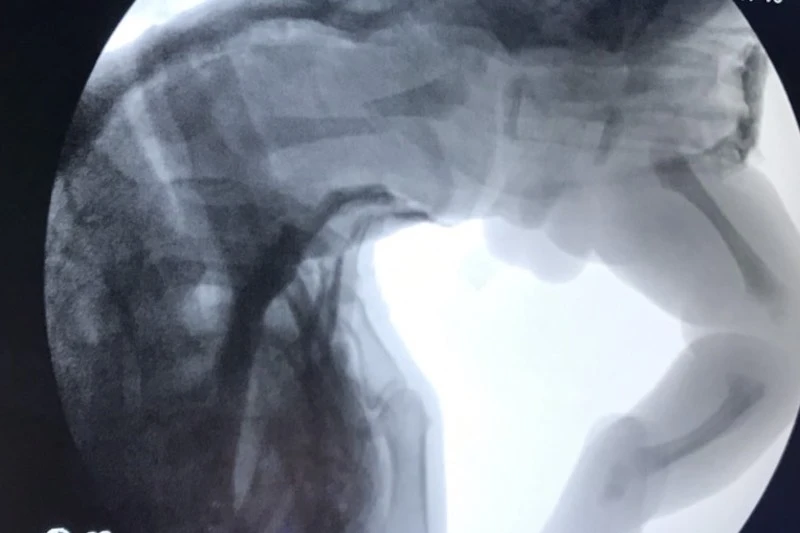

Hình ảnh chụp X-quang xác định bé bị gãy xương đùi trái. Ảnh: BV

Tuy nhiên, trong quá trình chăm sóc hậu phẫu, các BS phát hiện vùng đùi trái của bé sưng nề nhẹ nên chụp X-quang vùng chậu đùi trái. Kết quả xác định bé bị gãy xương đùi trái.

Các BS đã nén bó bột chậu đùi bàn chân trái cho bé. Sau bó bột, hình ảnh chụp X-quang không thấy biểu hiện di lệch, các ngón chân của bàn chân trái hoạt động tốt.